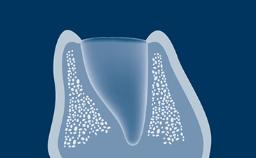

A osteotomia do implante é uma etapa cirúrgica essencial na implantodontia. Termina com a inserção de um implante dentário que posteriormente fornecerá ao paciente um substituto fixo ou removível para a ausência de dentes. Neste módulo, descreveremos primeiro a técnica correta de preparação óssea para a instalação do implante. Posteriormente, abordaremos os ajustes do protocolo necessários em diferentes densidades ósseas. Finalmente, discutiremos os riscos potenciais associados à técnicas inadequadas de osteotomia.

- selecionar o procedimento de perfuração apropriado para determinados tipos ósseos